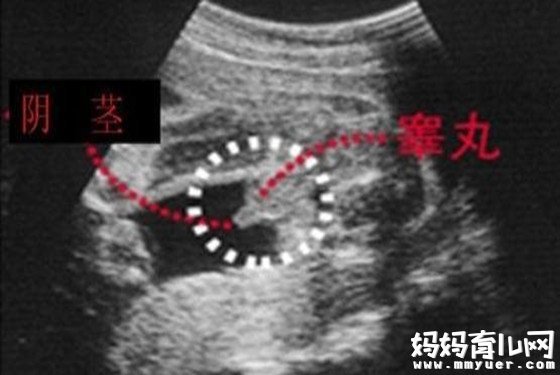

第三种:通过四维彩超图看清胎儿性别

男宝宝B超图

"凸出的东西"是他的标记:你们看到圆圆的是DANDAN,如果看到圆圆的加小肠的就是全部JJ

女宝宝的b超图

三条白线是明显的女宝特征,如果没有看到明显的三条白线,就看两腿之间有没有突出的东东,且中间有小凹槽的,就是女宝。